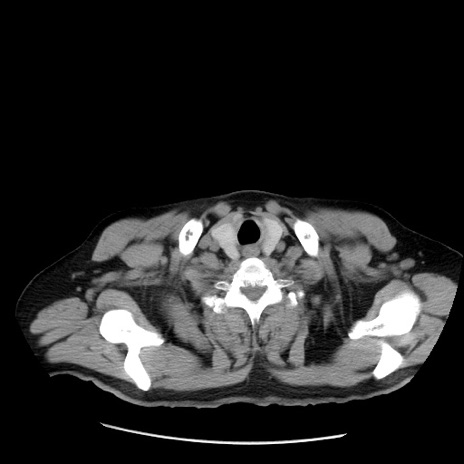

症例20(横断像)

【症例】 60歳代男性

【主訴】 腹部膨満、嘔吐

【現病歴】5日前頃より倦怠感を認め食事量減少し4日前の朝嘔吐、食事摂取困難となった。 3日前近医受診し点滴施行され整腸剤などを処方された。 当日他院を受診し、腹部膨満著明、炎症反応の上昇(CRP10.8、WBC11200)あり、紹介受診となる。

【既往歴】 躁うつ病(抗精神病薬多数内服あり)

【身体所見】 意識JCS1 受け答えがはっきりしないBP 111/57mHg、 P 67bpm、、BT35.2°C、SpO2 97%(RA)、 腹部:膨隆、打診で鼓音あり、全体的に圧痛有り、腸蠕動音(-)、反跳痛ははっきりせず。

【データ】WBC 11400、CRP 14.20